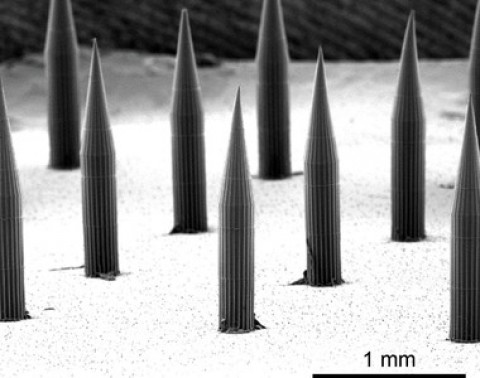

Microagulhas permitem depositar pontos quânticos sob a pele (Foto: Divulgação Kevin J McHugh MIT)

Microagulhas permitem depositar pontos quânticos sob a pele (Foto: Divulgação Kevin J McHugh MIT)

Os pesquisadores projetaram seu corante para ser entregue por um adesivo de microagulha, em vez de usar uma seringa e uma agulha tradicionais. Agora, esses patches estão sendo desenvolvidos para fornecer vacinas contra sarampo, rubéola e outras doenças. “Ao usar um fator de forma de microagulhas, essa plataforma deve ser facilmente assimilada no cenário futuro de vacinação, porque atualmente existem microagulhas em desenvolvimento para várias vacinas e mostraram vantagens como economia de dose de antígeno, estabilidade aprimorada de antígeno e facilidade de (auto) administração comparada às injeções solúveis tradicionais ”, comentaram os pesquisadores.

As microagulhas usadas no estudo relatado são feitas a partir de uma mistura de açúcar dissolvível e um polímero chamado PVA, além do corante de pontos quânticos e, se apropriado, da vacina. Quando o adesivo é aplicado na pele, as microagulhas, com 1,5 mm de comprimento, se dissolvem parcialmente, liberando sua carga útil em cerca de dois minutos.